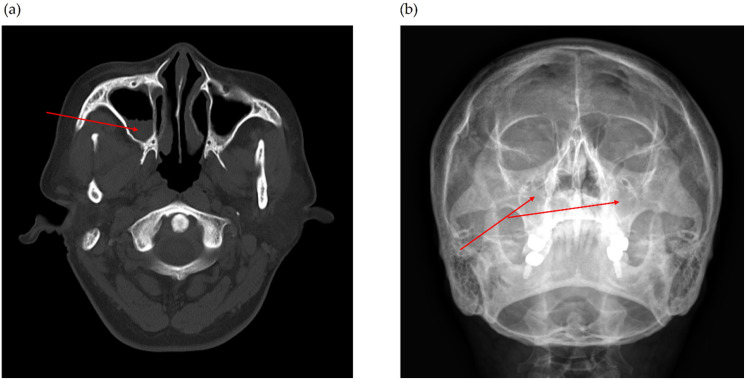

过敏性鼻炎(Allergic rhinitis, AR)和慢性鼻窦炎(chronic rhinosinusitis, CRS)是常见的上呼吸道疾病,经常共存。这些疾病虽然不会危及生命,但会显著降低生活质量,因其慢性和复发性而造成严重的社会经济负担,并对心理健康产生负面影响。在某些情况下,AR和CRS与包括自杀倾向在内的严重后果有关。本报告报告了两例年龄分别为42岁和37岁的女性,她们经历了反复发作的AR和CRS症状,如持续的鼻塞、鼻漏,导致吃饭时谈话困难和睡眠障碍,尽管接受了常规治疗,但持续了20多年。两例患者均接受8-12周的治疗方案,包括小天龙汤(SCRT)和针对蝶腭神经节(SPG)的超声引导针灸。采用鼻内窥镜检查结果、鼻结膜炎生活质量问卷评分和鼻总症状评分来评估治疗效果。观察到显著的治疗后改善,并且这些效果在停止治疗后持续了3个月,没有明显的不良事件报告。虽然鼻内皮质类固醇是AR和CRS的标准治疗方法,但大约30%的患者要么症状缓解不足,要么因不良反应而停止使用,这往往导致症状复发。相比之下,SCRT和spg靶向超声引导针灸联合治疗可能是一种有希望的替代治疗选择,显示出持续的症状改善而没有明显的不良反应。

Allergic rhinitis (AR) and chronic rhinosinusitis (CRS) are common upper respiratory tract diseases that frequently coexist. While not life-threatening, these conditions significantly diminish quality of life, impose substantial socioeconomic burdens due to their chronic and recurrent nature, and negatively impact mental health. In some cases, AR and CRS have been associated with severe outcomes, including suicidal tendencies. This report presents two cases of women aged 42 and 37 years who experienced recurrent AR and CRS symptoms, such as persistent nasal congestion, rhinorrhea, which led to difficulties in conversation during meals and sleep disturbances, for over 20 years, despite undergoing conventional treatments. Both patients received an 8-12 week treatment regimen consisting of Socheongryong-tang (SCRT) and ultrasound-guided acupuncture targeting the sphenopalatine ganglion (SPG). Treatment efficacy was assessed using nasal endoscopic findings, Rhinoconjunctivitis Quality of Life Questionnaire scores, and Total Nasal Symptom Scores. Significant post-treatment improvements were observed, and these effects persisted for 3 months after treatment cessation, with no significant adverse events reported. While Intranasal corticosteroids are the standard treatment for AR and CRS, approximately 30% of patients either experience insufficient symptom relief or discontinue their use due to adverse effects, often leading to symptom relapse. In contrast, the combination of SCRT and SPG-targeted ultrasound-guided acupuncture may offer a promising alternative treatment option, demonstrating sustained symptom improvement without significant adverse effects.